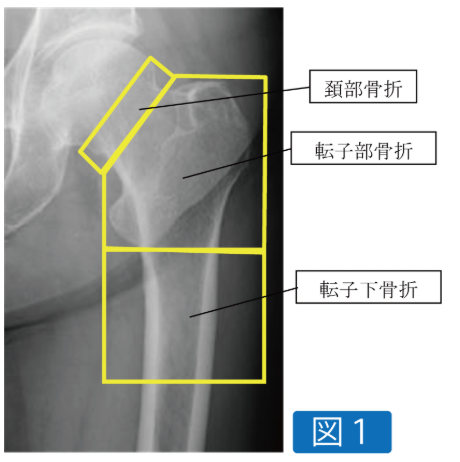

手術の方法は骨折の型によりますが、ずれの大きい頚部骨折は人工骨頭置換術(図2)、ずれの少ない頚部骨折はスクリュー固定(図3)、転子部や転子下骨折は髄内釘型の金具を使って手術することがほとんどです(図4)。しっかりと手術をして手術翌日から歩行練習等を始めることで、最近のデータでは入院は約1ヶ月程度となっております。